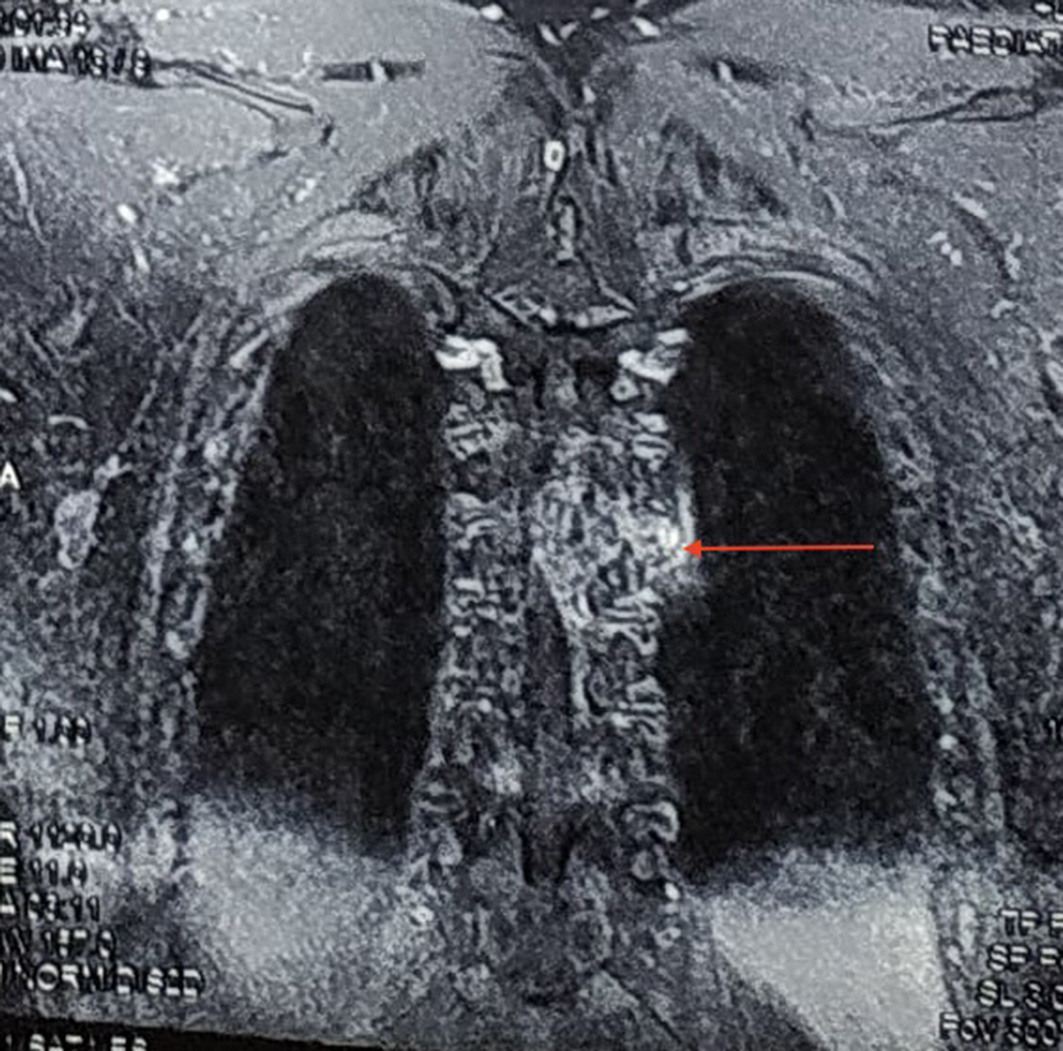

He had bladder and bowel incontinence. The remainder of his physical examination was within normal limits. Magnetic resonance imaging (MRI) of his spine revealed a T1 hyperintense and T2 hypointense lesion at the level of D4 vertebra. (Figures 1A, 1B, 2A and 2B). The lesion was homogeneously enhancing on contrast and was located intradurally and extramedullary on the left side. A differential diagnosis of metastatic lesion was made and thorough metastatic workup done, which however failed to show any primary tumour elsewhere.

Fig. 2A. Contrast-enhancing lesion at D4 (red arrow)

Fig. 2B. Coronal section image showing spinal lesion extending to the thorax (red arrow)